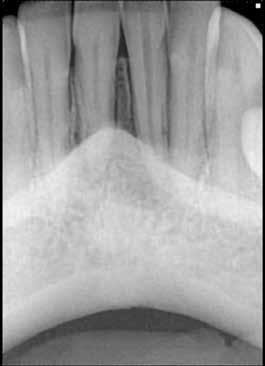

1. ábra: A 15-ös foggyökér meziális felszíne mellett látható radiolucens elváltozás, illetve a felvételen látható a korábban behelyezett gyökértömés, a parapulpális csap segítségével elhorgonyzott csonkfelépítés és a fogat borító cirkonkorona. –2. ábra: A saggitalis irányú CBCT-metszeten jól megfigyelhető az állcsontgerincet elérő radiolucens elváltozás. – 3. ábra: Az axiális irányú CBCT-metszeten egyértelműen látható a kezeletlen palatinális gyökércsatorna, valamint a radiolucens elváltozás mezio-disztális kiterjedése is jól megítélhető. – 4. ábra: A palatinális gyökércsatorna szelektív endodonciai kezelése során először gyógyszeres zárás került behelyezésre. – 5. ábra: A gyógyszeres zárás során alkalmazott kalcium-hidroxid alapú paszta a szulkuszon keresztül a szájüregbe extrudálódott. – 6. ábra: A gyökértömő anyag a középső és apikális gyökéri harmad határán lévő laterális csatornán keresztül a periapikális térbe extrudálódott. 7. ábra: A kezelések befejezését követően 4 évvel készült röntgenfelvételen jól látható a csontállomány gyógyulása és a fiziológiás gyökérhártyarés újbóli kialakulása. –8. ábra: A peroperatív CBCT-felvétel alapján készített koronális irányú metszeten jól látható a gyökércsúcs körül lévő periapikális felritkulás. – 9. ábra: A kezelések befejezése után 4 évvel készített CBCT-felvételen a gyulladásos lézió teljes megszűnése észlelhető.

A CBCT-készülékek endodonciai alkalmazásának talán az az egyik legnagyobb előnye, hogy így olyan anatómiai struktúrák is láthatóvá válnak, amelyeket egyébként nem tudnánk detektálni panoráma, cephalo, vagy periapicalis felvételek segítségével. Mivel a CBCT-felvételek kiértékelése számítógép segítségével történik, így a felvételek vizsgálata során lehetőségünk van az adott területet több nézőpontból és több síkban is megvizsgálni. 2015 októberében egy korábban a rendelőnkben kezelt 55 éves férfi páciens azzal a céllal kereste fel ismét a rendelőnket, hogy másodvéleményt kérjen egy jobb felső kvadránsban található fogával kapcsolatban. Egy másik rendelőben történő vizsgálat során a panaszos fog törését vélelmezték és a fog eltávolítását javasolták, illetve arról is beszámolt, hogy az elmúlt hét során ezen a területen egy puha duzzanat is kialakult. A klinikai vizsgálat során a jobb felső első és második kisőrlő között (14–15) egy fluktuáló duzzanatot észleltünk az áthajlásban. Az 15-ös fog mesialis oldalán 12 mm mély tasakot szondáztunk. A páciens által hozott periapicalis felvételen a 15-ös fog gyökércsúcsának mesialis részén egy nagy kiterjedésű radiolucens elváltozás volt észlelhető (1. ábra). A saggitális síkban vizsgált CBCT-felvételen (Carestream CS 9000, Carestream Dental) a lézió valódi kiterjedése is láthatóvá vált (2. ábra). A megelőző endodonciai kezelések során csupán a bukkális csatorna került detektálásra és gyökértöméssel való ellátásra. Az axiális irányú CBCT-szeleteken egyértelműen látható volt az ellátatlan palatinális gyökércsatorna (3. ábra)

Először kalcium-hidroxid alapú ideglenes gyógyszeres zárás került a palatinális csatornába (UltraCal XS, Ultradent Products; 4–5. ábra), amelyet 6 hét után a végleges gyökértömés elkészítése előtt eltávolítottunk. A gyökértömés elkészítése során meleg vertikális kondenzációs technikát alkalmaztunk. Radiológiai felvételen megfigyelhető volt, hogy a gyökértömő anyag egy laterális csatornán keresztül kis mennyiségben a periapicalis térbe extrudálódott (6. ábra). A 4 évvel később készített kontrollfelvételeken a lézió gyógyulása volt megfigyelhető (7–9. ábra). A vizsgálati eredmények és a kezelés kimenetele egyértelműen igazolta, hogy nem gyökérfraktúrával álltunk szemben, tehát a kezdeti diagnózis tévesnek bizonyult. Ez is azt erősíti, hogy korlátozott mennyiségben rendelkezésre álló adatok alapján nem lehet pontos diagnózist felállítani. Manapság szinte elengedhetetlen a CBCT-felvételek endodonciai beavatkozások során történő használata, feltéve, ha ezek elkészítése során az ALARA elv (as low as reasonably achievable) betartásra kerül.